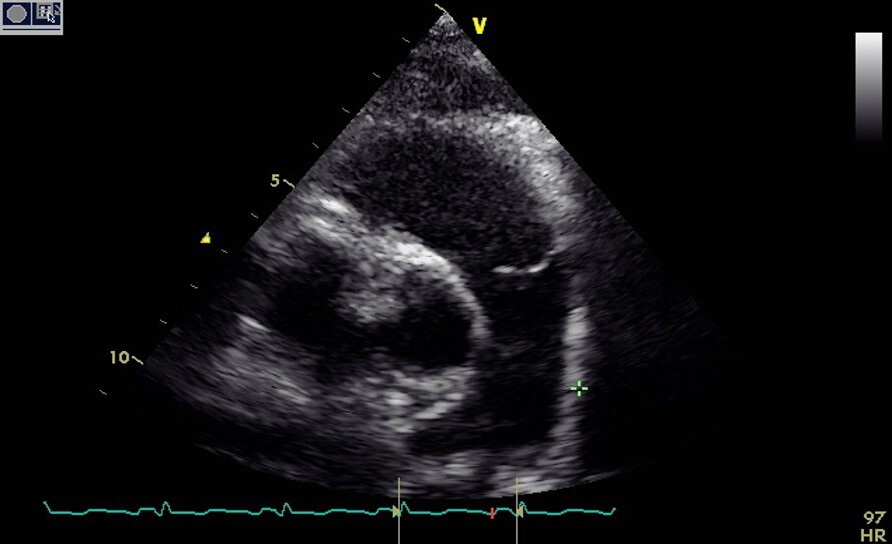

What should see during the PSAX MV window? 6

1. RV free wall 2. RV chamber 3. IVS 4. AMVL 5. PMVL 6. MV annulus

The MV posterior leaflet edge should appear how during PSAX MV level?

Equidistant from all sections of the posterior wall. *Not lopsided*

How should the LV appear during the PSAX mid (pap) level?

LV should appear round

How should the Pap muscles look during the PSAX Mid (pap) level?

**Should both be attached to the LV wall** If not we are off rotation and most likely over rotated too far clockwise

What are structures we should see in the PSAX mid (pap) level? 6

1. RV free wall 2. RV chamber 3. IVS 4. two Pap muscles (Anterolateral and Posteromedial) 5. Pericardium 6. All walls of the mid LV simultaneously